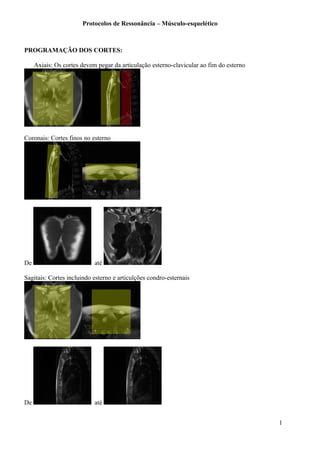

PROGRAMAÇÃO DOS CORTES:

Axiais: Os cortes devem pegar da articulação esterno-clavicular ao fim do esterno

Coronais: Cortes finos no esterno

Sagitais: Cortes incluindo esterno e articulções condro-esternais